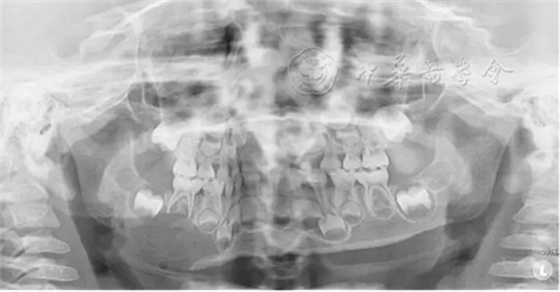

(1)疾病定義及口腔表現(xiàn):LCH是一組原因不明、以朗格漢斯細胞及其前體細胞克隆性增生為特點的疾病,又稱組織細胞增生癥X(histiocytosis X)。多見于20歲以下青少年。根據(jù)患者的發(fā)病年齡和臨床特點將其分為3型:嗜酸性肉芽腫、漢-許-克病和勒-雪病??谇活M面部常見的為骨嗜酸細胞肉芽腫,好發(fā)于下頜磨牙區(qū)與下頜角部位,病變主要為溶骨性破壞。早期表現(xiàn)為慢性炎癥和局部無痛性膨隆,病變區(qū)牙槽黏膜糜爛、潰瘍;牙齦充血,形成深牙周袋。隨著病變進展,出現(xiàn)牙齒松動加重,病變區(qū)鈍痛,進食時加劇,口臭明顯。拔除松動牙后拔牙創(chuàng)經久不愈,觸碰牙槽窩時疼痛劇烈。影像學檢查可見骨內圓形或橢圓形低密度影(圖2),直徑數(shù)毫米至數(shù)厘米不等,邊緣較囊腫模糊。頜骨內病損常延伸至牙槽嵴,形成牙齒懸浮的特征性影像。牙槽骨包括牙槽中隔呈水平或垂直向吸收,牙根吸收。

圖2 4歲朗格漢斯細胞組織細胞增生癥患兒的曲面體層X線片,可見右側下頜骨大面積橢圓形低密度影